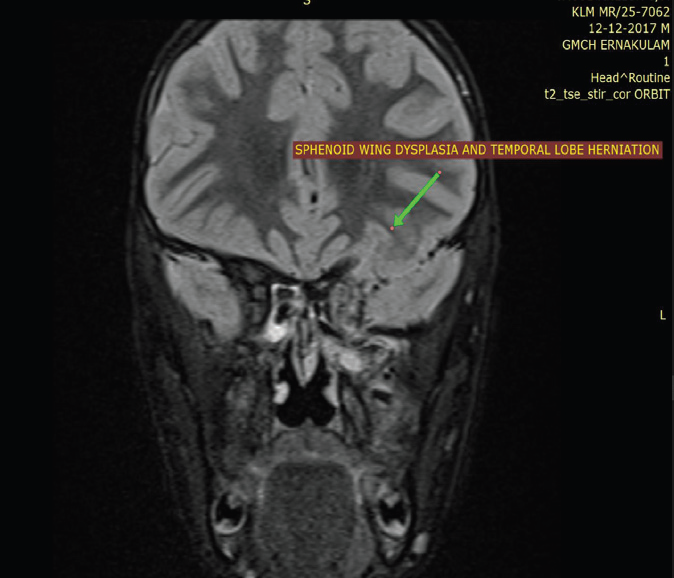

An 8-year-old boy, born to a mother with neurofibromatosis type

asymmetry of the globes without acute visual deficit.MRI of the brain and orbits with contrast, supplemented by CT imaging, revealed dysplasia of the left sphenoid wing with anterior herniation of the left temporal lobe into the posterior aspect of the left orbit, consistent with an orbital encephalocele. This resulted in leftsided proptosis and mild asymmetric enlargement of the left globe.

The left medial and lateral rectus muscles were enlarged and demonstrated post-contrast enhancement, suggestive of extraocular

Figure 6:MRI orbit, axial and coronal post-contrast fat-suppressed T1-

weighted image shows enhancing enlargement of the left medial and

lateral rectus muscles (arrows) with mild surrounding orbital fat stranding,

suggestive of extraocular muscle neurofibroma in the background of

neurofibromatosis type 1.

Figure 7:MRI orbit, coronal T2-weighted image of an 8-year-old boy

suspected to have NF-1 demonstrates anterior herniation of the left

temporal lobe into the posterior portion of the left orbit, consistent with an

orbital encephalocele, resulting in left-sided proptosis and mild asymmetric

enlargement of the left globe.

muscle neurofibromas, with mild surrounding orbital fat stranding.

The intraorbital segment of the left optic nerve appeared mildly

tortuous but showed no enlargement or abnormal enhancement.

CT demonstrated absence of tram-track calcification, excluding

optic nerve sheath meningioma. The left superior orbital fissure was

asymmetrically enlarged, and the left sphenoid sinus was hypoplastic.

MRI of the brain demonstrated multiple non-enhancing T2/ FLAIR hyperintense lesions involving the bilateral globus pallidi, thalami, cerebellum, and cerebral peduncles, characteristic of FASI. No diffusion restriction or mass effect was observed. As in the first case, the lesion had previously been interpreted as an arachnoid cyst.

Given the patient’s age and absence of visual compromise, a conservative approach with close ophthalmologic and radiologic surveillance was recommended.